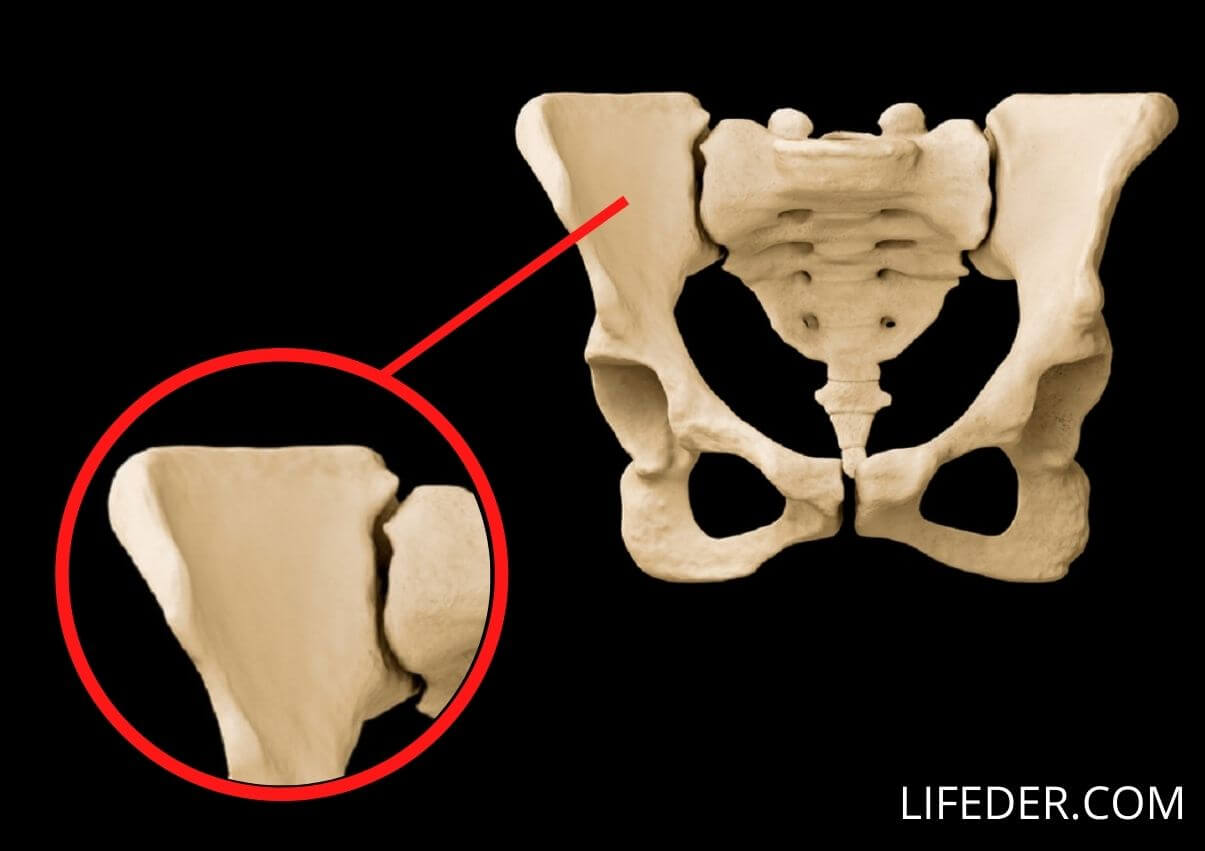

Los huesos de la pelvis

Los huesos de la pelvis incluyen el hueso ilion, el hueso isquion y el pubis. Estos huesos se organizan en dos cavidades: la pelvis mayor y la pelvis menor.

Este conjunto de huesos proporciona soporte estructural al cuerpo y permite que las personas se mantengan en pie.

Asimismo, es la zona de fijación de diversos músculos, incluyendo los músculos del abdomen y los músculos de la espalda. Además, estos huesos protegen ciertos órganos internos como la vejiga.

1- El ilion

El ilion se encuentra en la parte superior de la estructura pélvica. Está compuesta por la cresta ilíaca y por las espinas ilíacas.